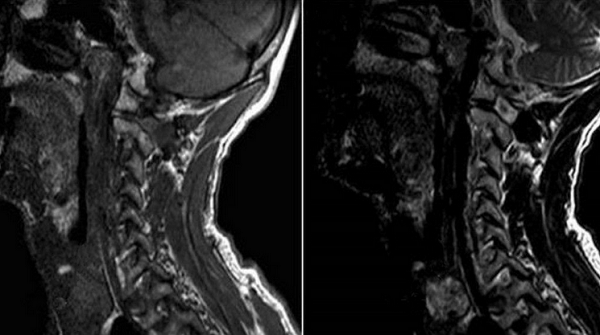

Снимки МРТ мягких тканей шеи

Проведение магнитнорезонансной томографии с использованием различных режимов повышает информативность исследования рыхлых элементов. Изучение особенностей кровоснабжения зоны интереса и диагностика новообразований требуют применения контрастного раствора. В качестве «окрашивающего» препарата используют хелаты гадолиния.

Мягкие ткани шеи на МРТ

Магнитно-резонансное сканирование может применяться в качестве основного или дополнительного метода исследования в диагностике эндокринных заболеваний.